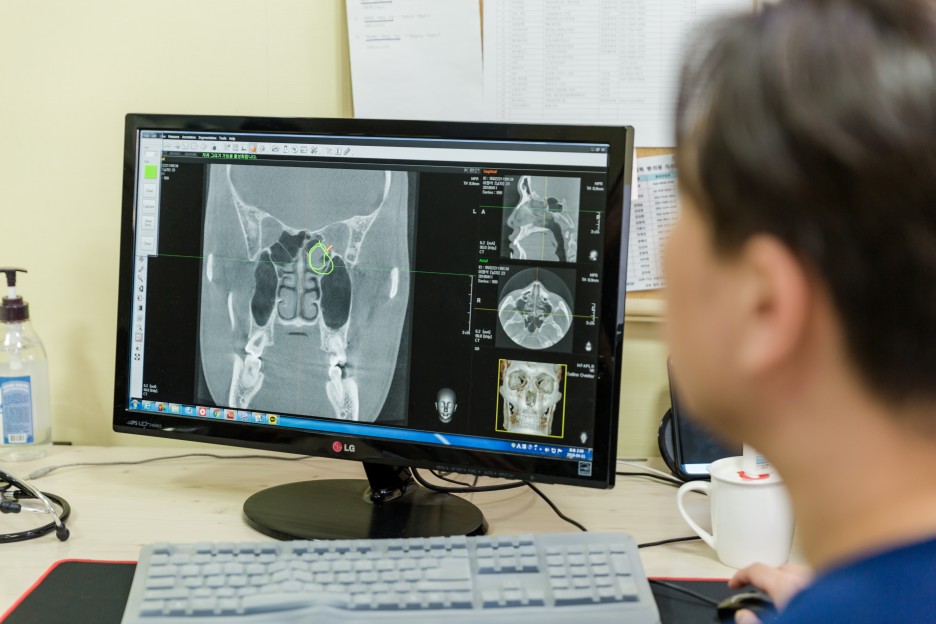

삶의 질을 계속 망가뜨리는 부분이 많아서 충농증 수술 후 결과를 다양하게 확인하는 것도 중요하지만 이런 경우 3D-CT 같은 장비에서 어느 정도 문제가 있는지 확인하고 꼼꼼히 이를 체크하는 것이 우선적이라고 할 수 있습니다. 염증이나 주변 조직을 보고 개개인에 맞는 진료를 하는 것이 올바른 선택이었습니다.

코라는 부위는 민감한 부위였고, 부빙동이라는 부위는 코 내부 안쪽에 위치하고 있어 보다 꼼꼼한 관리가 적용되어야 했습니다. 주위의 신경과 점막, 지지대까지 고려하여 면밀히 조사하는 곳을 선택하는 것이 올바른 판단이었습니다.

저희 병원에서는 비염과 축농증에 대한 세심한 관리 프로그램을 준비하고 있기 때문에 걱정도 줄일 수 있었습니다. 축농증 치료는 복잡한 코 내부 구조를 의료진이 확인하고 집도하는데 정교한 장비가 요구됐는데요. 축농증 상황에 맞게 가느다란 장비를 사용하여 보다 세밀하게 코 구조를 체크하여 진행하고 있기 때문에 보다 만족감 높은 결과를 만들 수 있었습니다. 더욱이 염증이 있는 부분만 선택적으로 치료해 짧은 시간에 얻은 결과를 기대할 수 있었습니다.